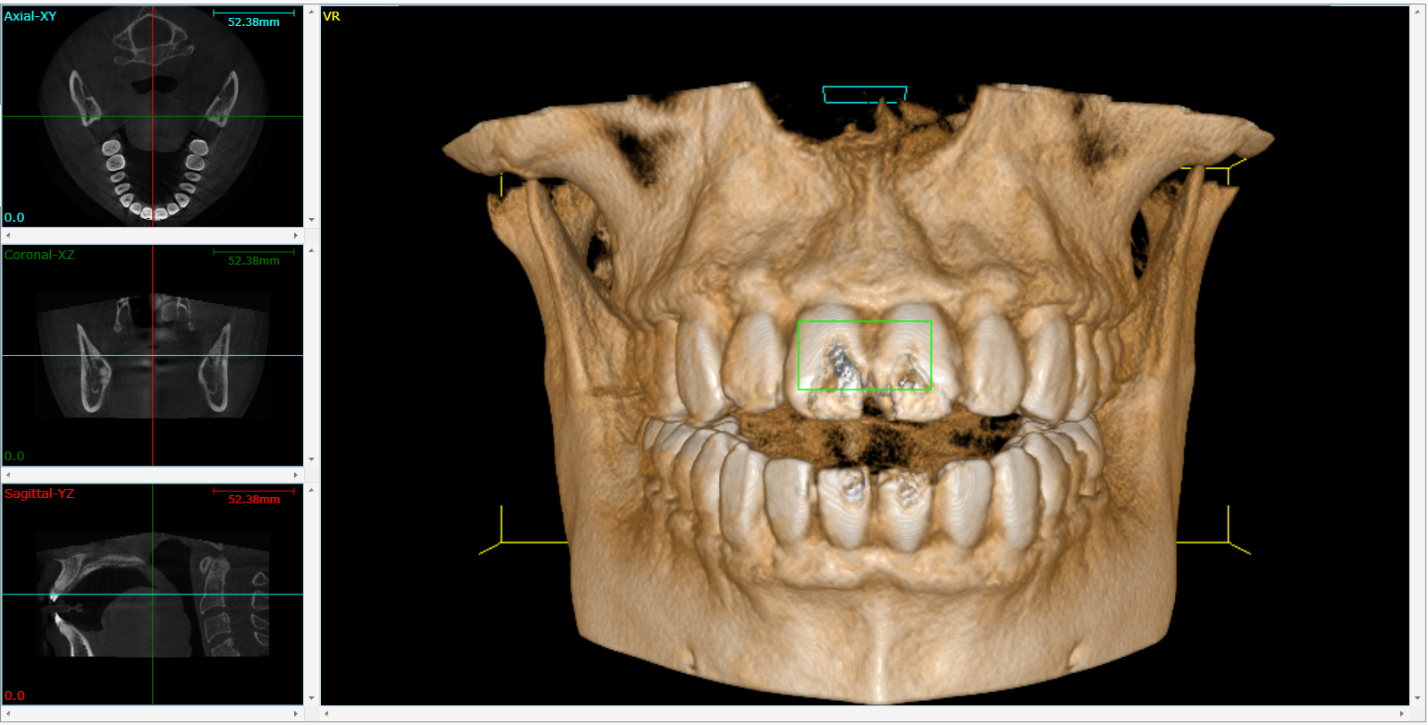

Zebris vs. Static Imaging (X-rays, CBCT):

- Static imaging shows anatomical structures but not functional movement

- Zebris captures dynamic function but not detailed anatomy

- Combined approach often provides the most comprehensive diagnosis